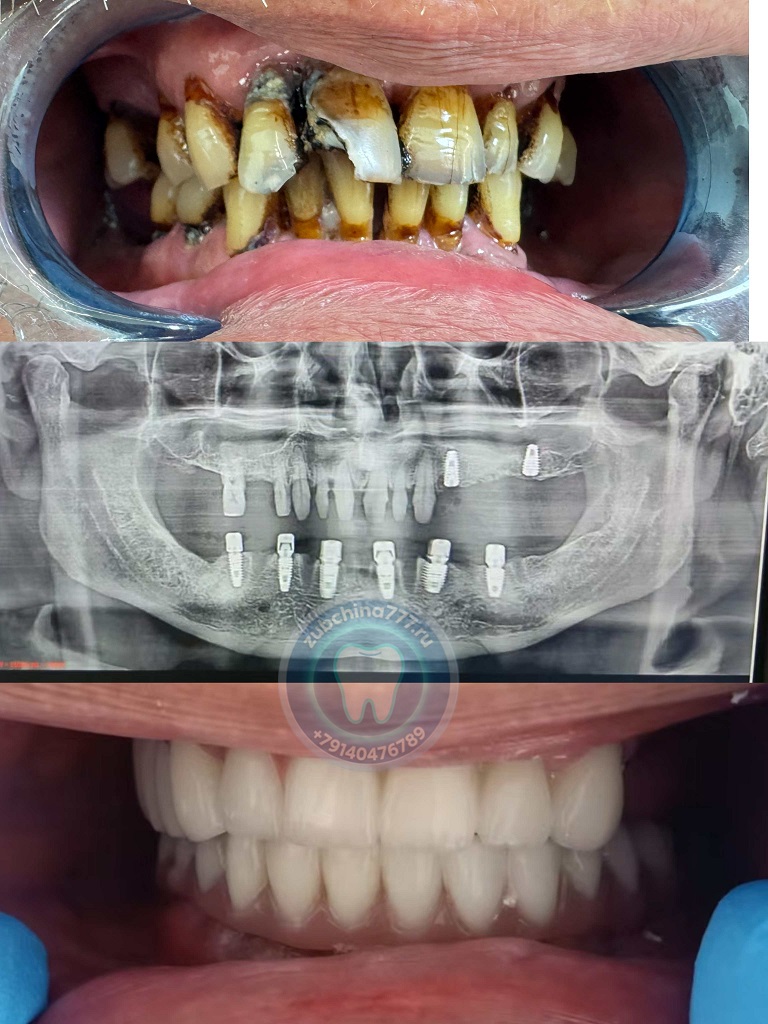

Фотографии пациентов ДО и ПОСЛЕ лечения и протезирования зубов в Хэйхэ